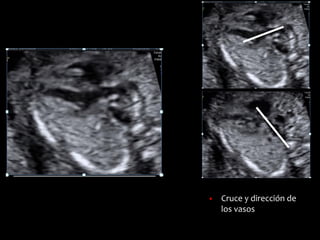

▪ Cruce y dirección de

los vasos